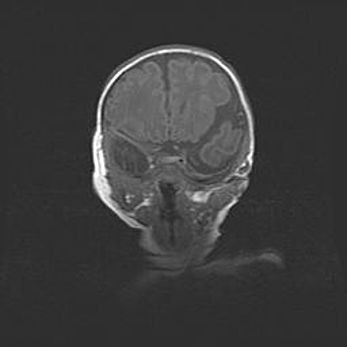

Открытая гидроцефалия.

Возраст: 9 месяцев 12 дней

Вес: 6800 г

Пол: мужской

Окружность головы: 41,5 см

Срок гестации: 28 недель

Гидроцефалия головного мозга у новорожденных имеет характерный признак: опережающий рост окружности головы приводит к визуально хорошо определяемой гидроцефальной форме сильно увеличенного в объёме черепа. Детские неврологи определяют следующие симптомы гидроцефалии у грудничков: выбухающий напряжённый родничок, частое запрокидывание головы, смещение глазных яблок к низу.